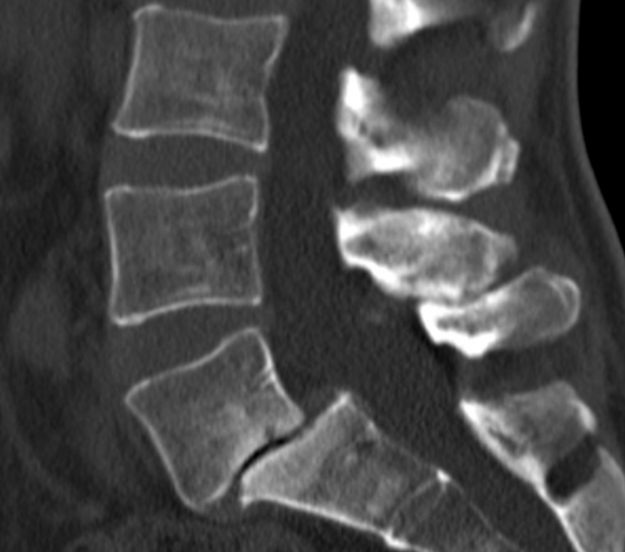

Ασθενής άδρας 33 ετών με έντονη οσφυαλγία απο 12μήνου και επιδείνωση από διμήνου. Ο απεικονιστικός έλεγχος ανέδειξε σπονδυλολίσθηση 2ου βαθμού σε έδαφος σπονδυλόλυσης στο ύψος Ο5-Ι1. Διενεργήθη διαδερμική (ελάχιστα επεμβατική) σπονδυλοδεσία στο επίπεδο Ο5-Ι1 Ο ασθενής παρουσίασε σημαντική βελτίωση της συμπτωματολογίας του. Εξήλθε του νοσοκομείου την 3η μετεγχειρητική ημέρα. Προεγχειρητική Αξονική Τομογραφία Μετεγχειρητική Αξονική Τομογραφία…